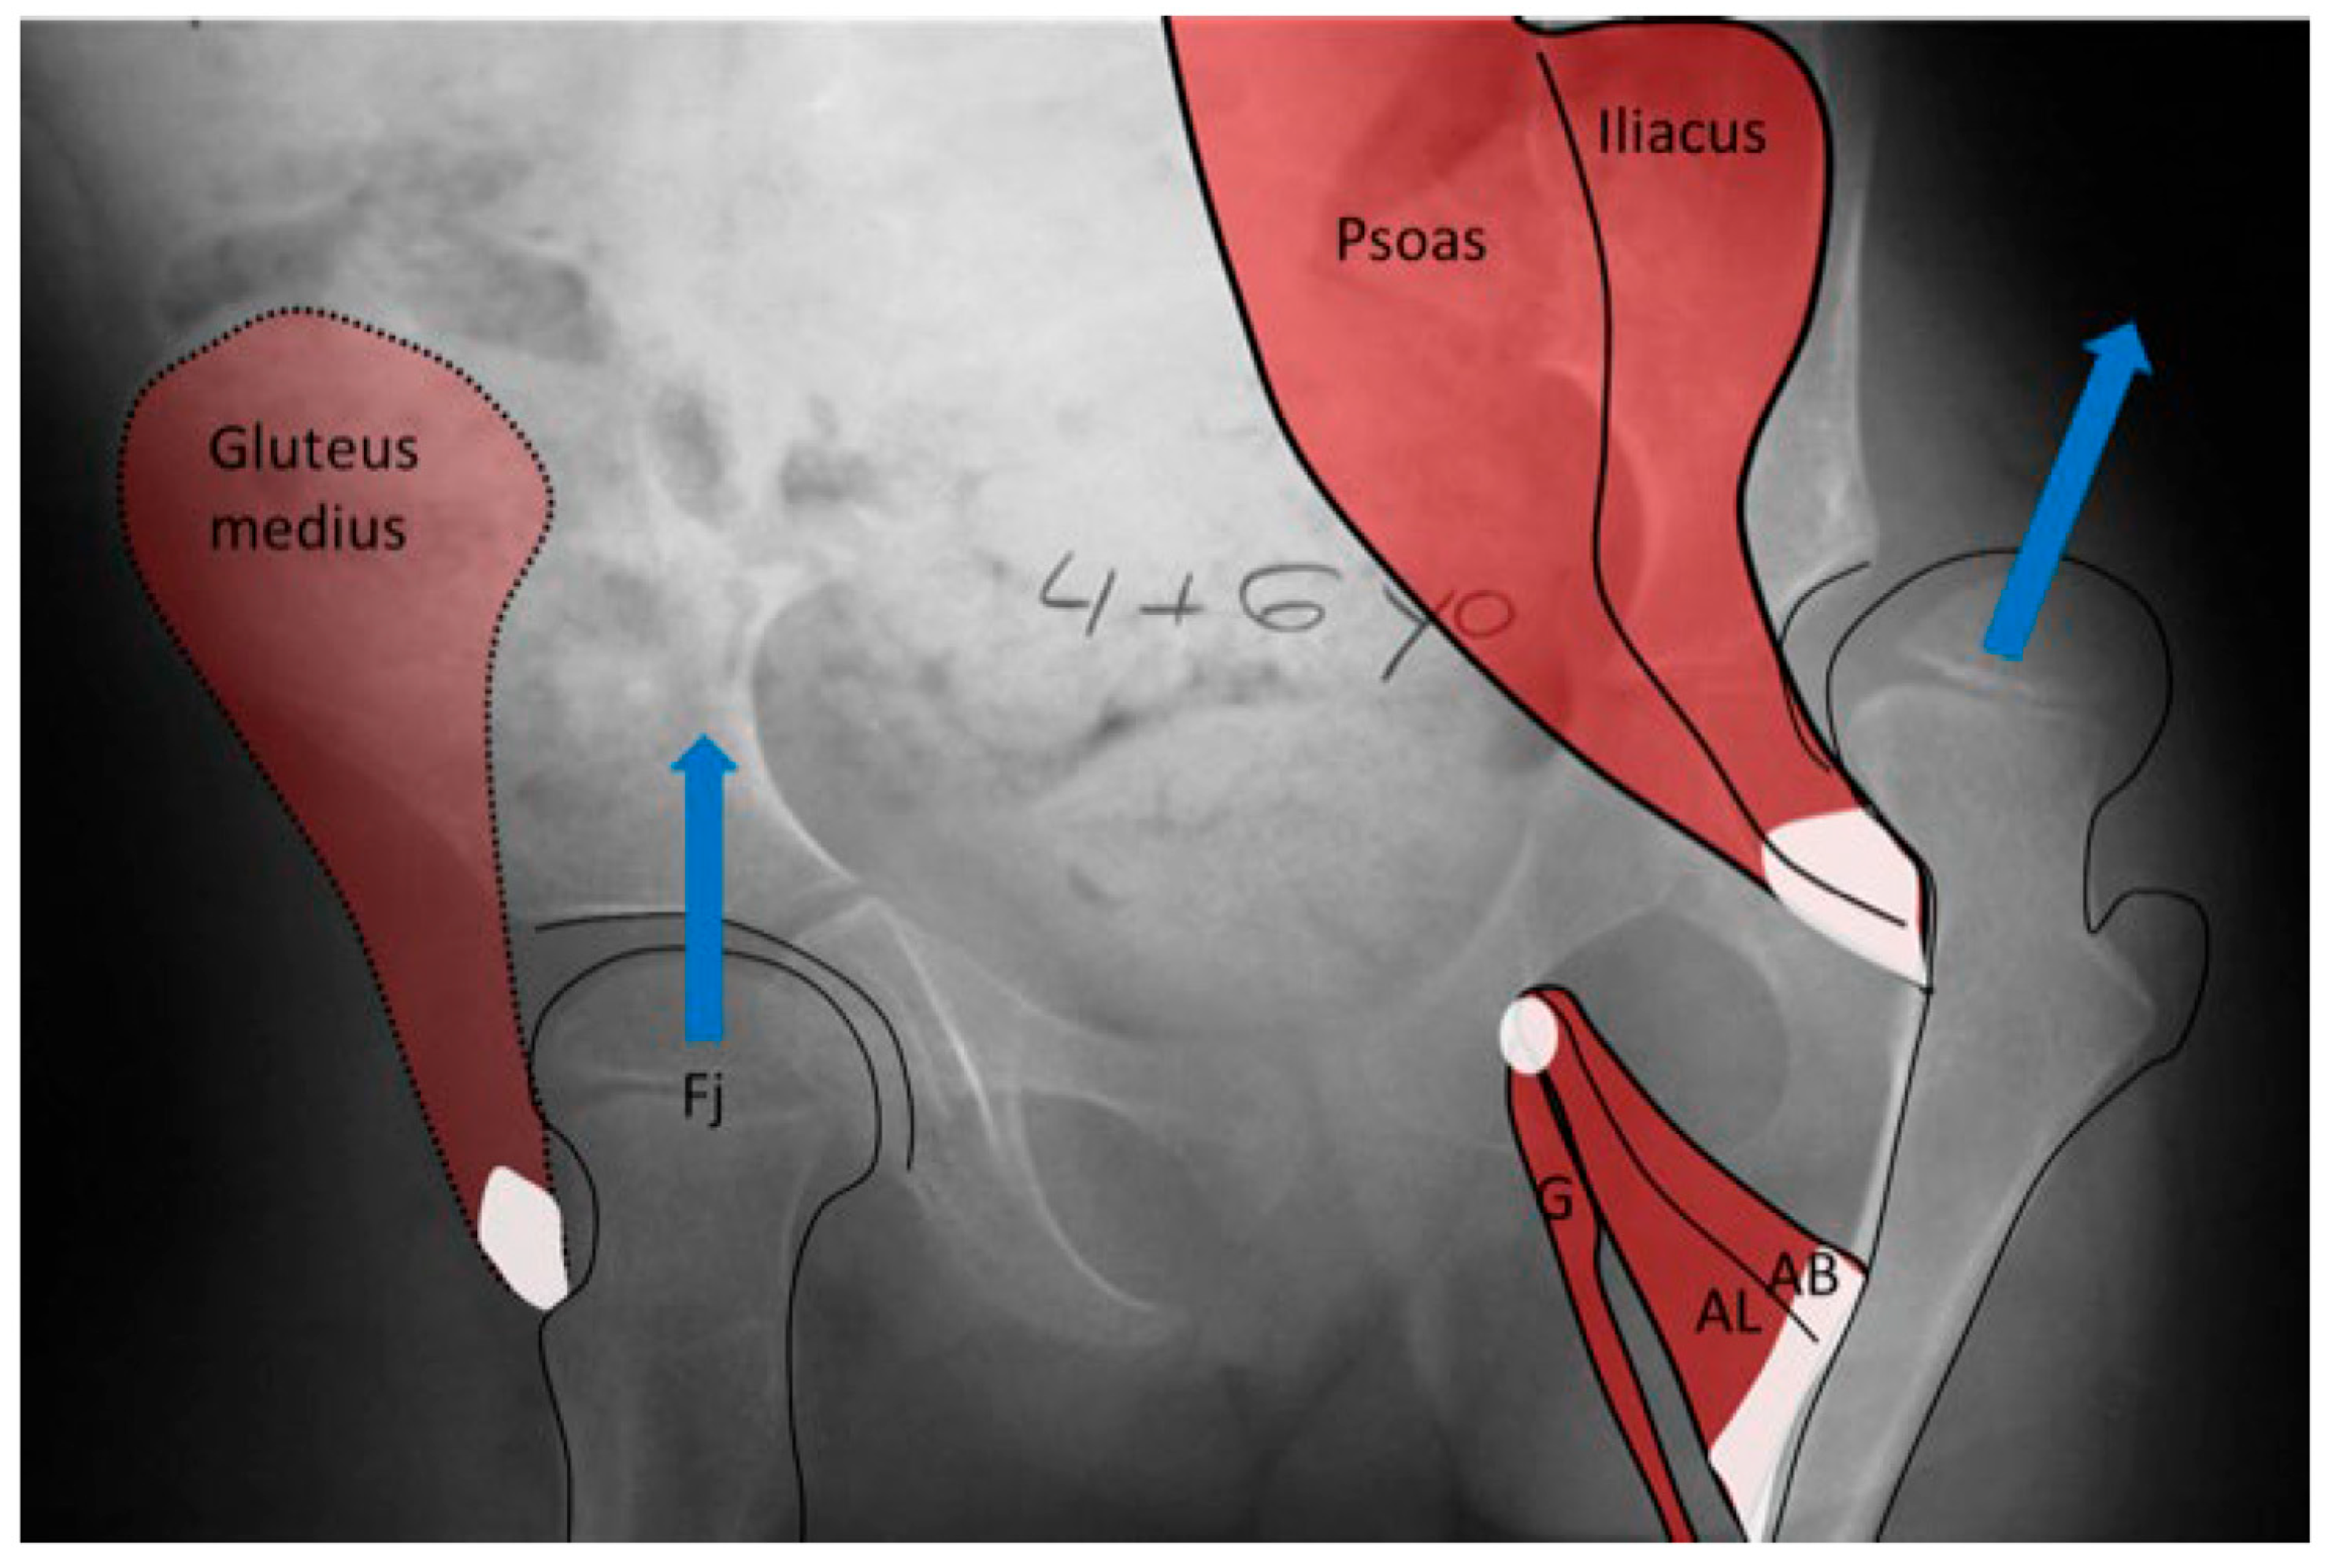

3.2. Biomechanical Considerations

3.2.1. Normal Development

3.2.2. Biomechanical Principles Driving Femoral Shape Development